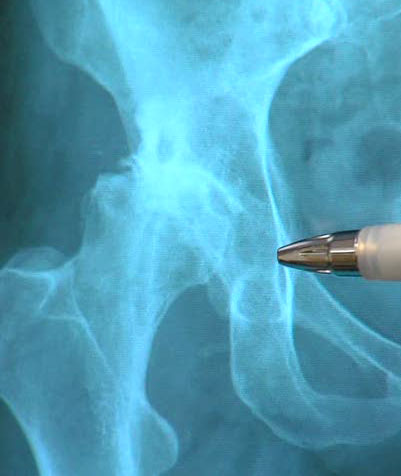

My X-ray told the story. I was experiencing severe pain, and the X-ray shows there was no cartilage left in my right hip joint and the bone was deteriorating.